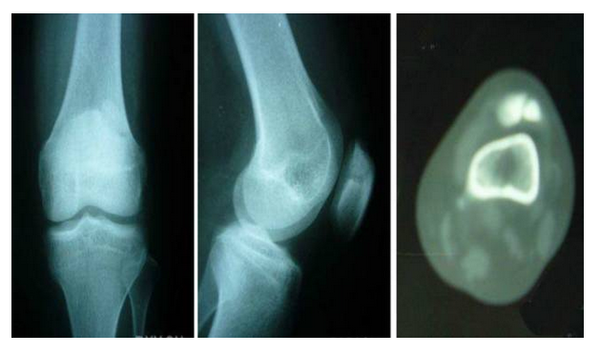

6、股骨头骨骺滑脱

膝关节的牵涉痛,儿童和十几岁的少年,膝关节疼痛的定位不清,没有膝关节外伤史,体重超重,受累髋关节轻度屈曲外旋,被动内旋和伸直受累髋关节可引发疼痛,膝关节检查正常,典型的X线表现为股骨头骨骺移位,临床表现典型但摄片阴性不能排除诊断,此时CT扫描有助于诊断。